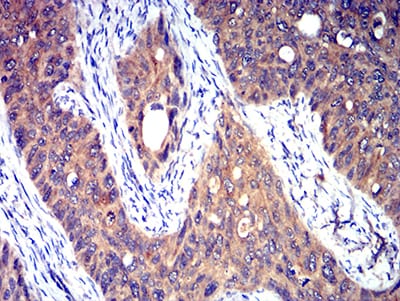

分类: 科研抗体货号: 31313别名: TR; HTR; CF2R; PAR1; PAR-1应用: IHC反应种属: Human